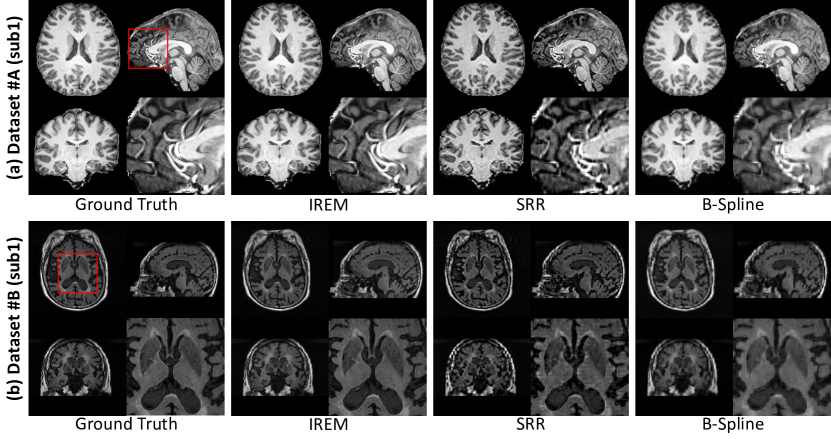

Refer to caption

Figure 5: Qualitative results of B-spline interpolation, SRR [4], and IREM on dataset #A (sub1) and #B (sub1). Here the factor k𝑘k of down-sampling is 4.

3.3.2 Performance on simulation validation.

On dataset #A, the quantitative evaluation results of B-spline interpolation, SRR [4], and IREM are shown in Figure 4 (a). We indicate that IREM consistently outperforms the two baselines at all factors k𝑘k of down-sampling in terms of all metrics. Figure 5 (a) demonstrates that the representative slices of an HR image (#A sub1) reconstructed from the three methods, and the results from IREM visually are closest to GT HR image.

On dataset #B, the quantitative and qualitative evaluation results of the three methods are shown in Figure 4 (b) and Figure 5 (b), respectively. We can see that IREM achieves the best performance, which is consistent with the experiments on dataset #A.